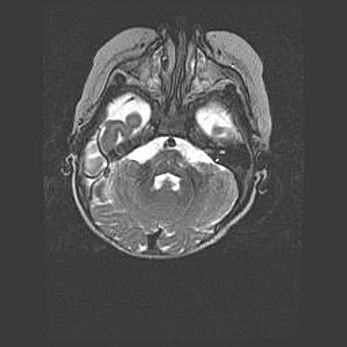

Церебральная ишемия II.

Возраст: 5 дней

Вес: 3400 г

Пол: женский

Окружность головы: 35 см

Срок гестации: 39 недель

Церебральная ишемия – это заболевание, характеризующееся недостаточностью (гипоксией) либо полным прекращением (аноксией) снабжения мозга кислородом по причине закупорки одного или нескольких сосудов. Это приводит к  что метаболическим расстройствам различной степени тяжести в тканях головного мозга, развитию коагуляционных некрозов и гибели нейронов.